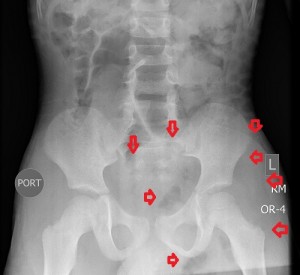

The 1st image in the top panel is a plain radiograph of the child’s pelvis depicting enlargement of the left hemipelvis and shift of the pelvic structures to the right due to a poorly-revealed mass with patches of fat in it. The 2nd and 3rd images in the top panel are CT images of the pelvis and they show a multilobulated mass centered in the left ischiorectal fossa and perineum infiltrating the lower retroperitoneum, medially, and the left gluteal muscles, laterally. Its medial extent is well-defined and similar in attenuation to subcutaneous fat, while its lateral extent is less defined and of soft-tissue attenuation. The mass compresses the rectum while displacing it to the right and pushes the urinary bladder upwards. There is no bony invasion or destruction.